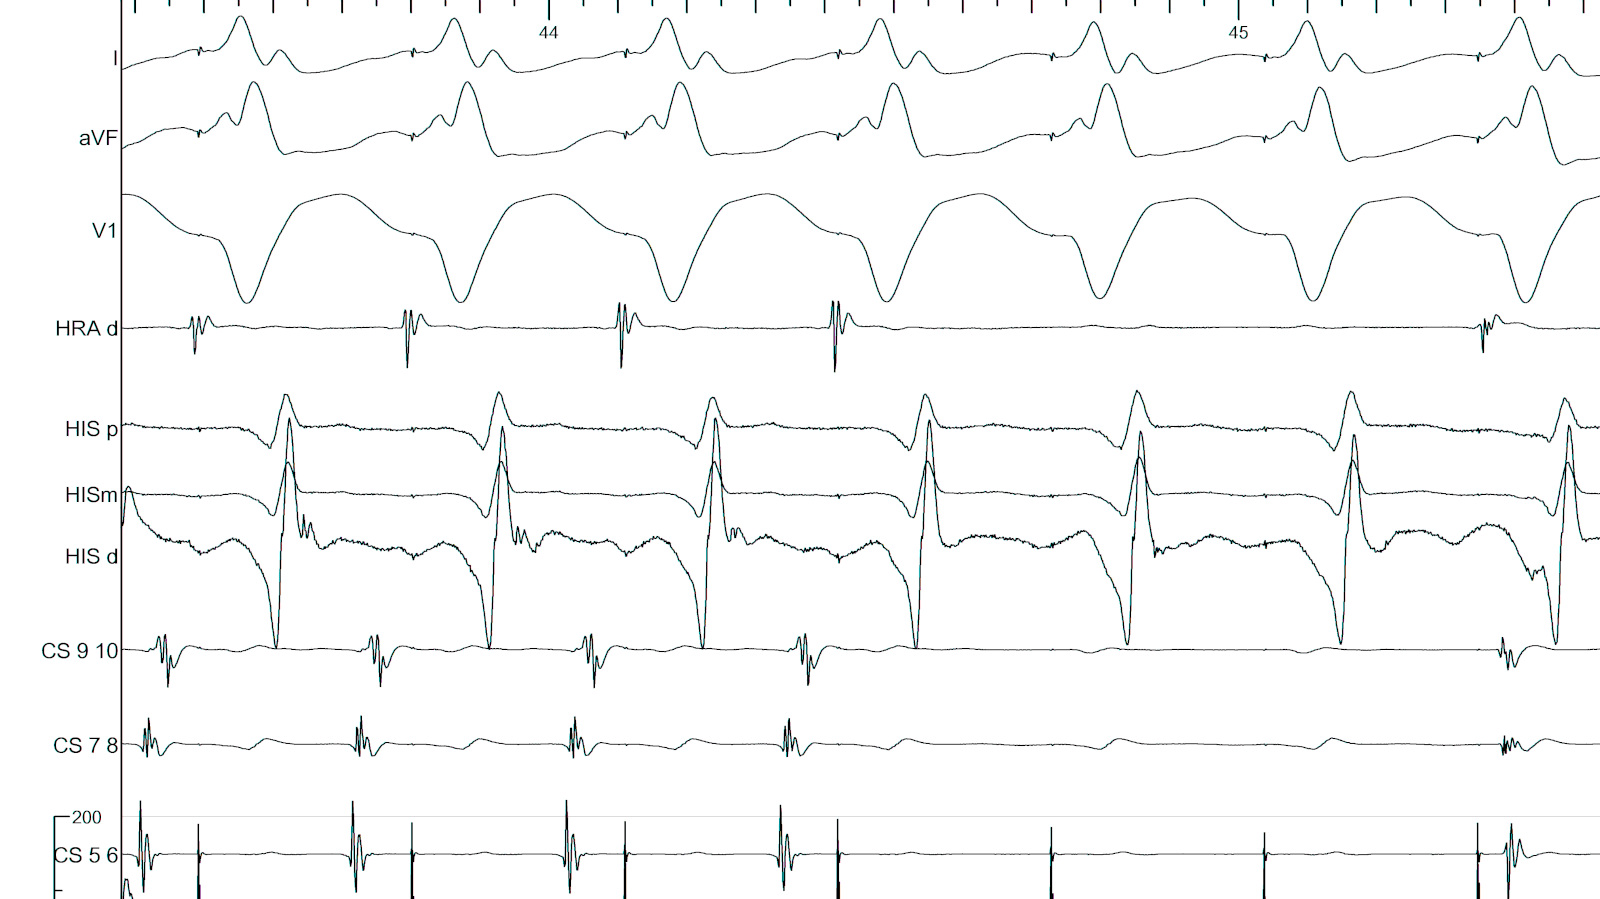

LA-CS potential to identify endocardial / epicardial

epicardial_ap_signal_sequence.jpg

la_cs_block.jpg